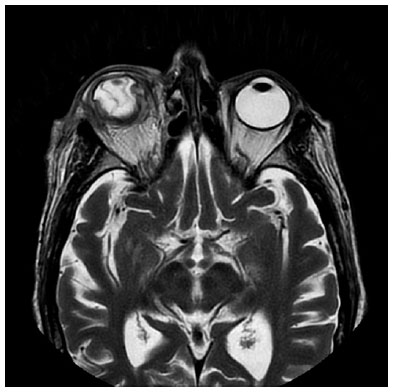

Seventy-two hours from the onset of the symptoms, the RE developed an ischemic necrosis of the anterior segment that led to a spontaneous corneal perforation (Figure 2). A new orbital MRI was performed to search for an orbital or subperiostic abscess, without any findings suggestive of its presence (Figure 3).